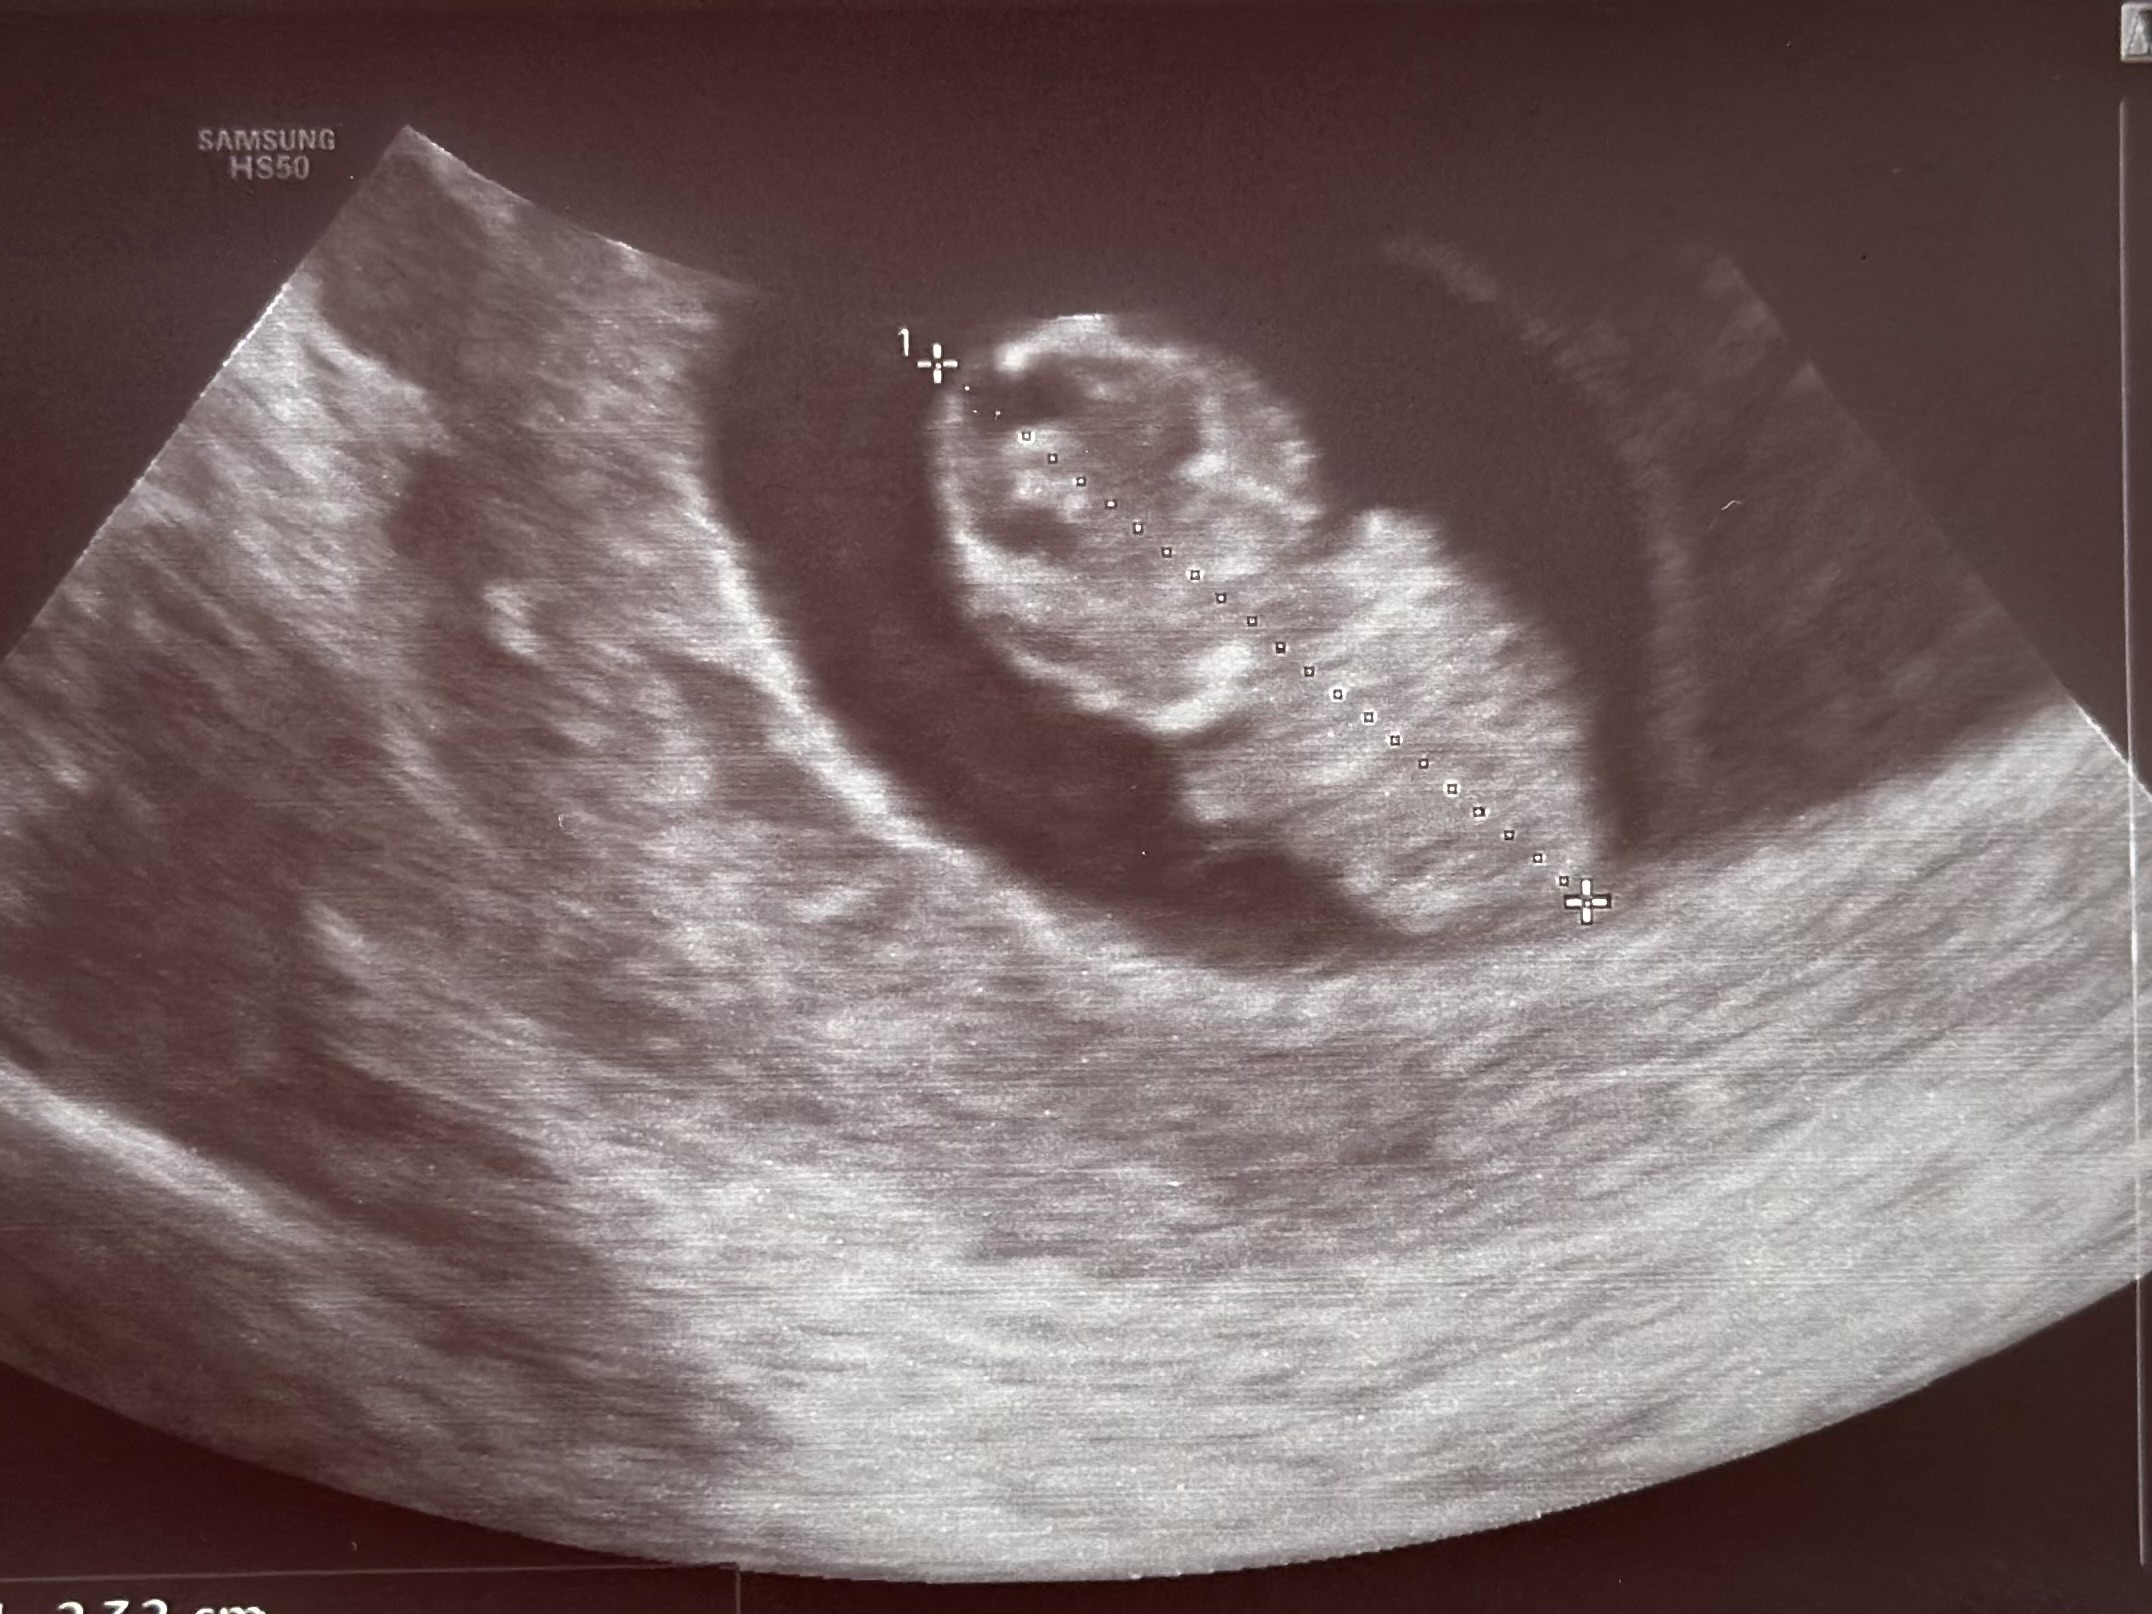

plamienie było albo kontaktowe po seksie albo z uwagi na to, że miałam bardzo niejednorodne endometrium i się coś tam jeszcze oczyszcza - ale z wizyty na wizytę przebudowuje się i coraz lepiej wygląda, a bąbel rośnie idealnie 🥹

wg usg dziś 9+0

Załączniki

• IMG_8622.jpeg

IMG_8622.jpeg

554,9 KB · Wyświetleń: 28